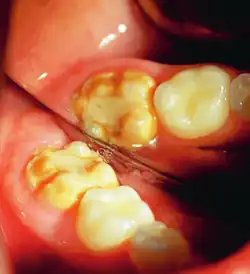

It occurs as a result of severe hypomineralization of the enamel as the enamel appears intact in the initial stages but gradually chips and fractures after the tooth erupts due to the weakened mineral content hence, leading to the formation of rough surfaces and cavities which makes the tooth highly vulnerable to undergo wear, decay and sensitivity.[26] Notably, the post-eruptive breakdown is linked to severe forms of hypomineralization like molar incisor hypomineralization (MIH).[27]

MIH is a specific pattern for which first permanent molars and permanent incisors are affected with the presence of demarcated opacities on the teeth with variations in color from white to yellow and brown.[28] Besides, the enamel which is affected becomes weaker and hence the teeth becomes highly sensitive and likely to undergo post-eruptive breakdown. Notably, the severity of MIH varies among individuals as some experience minimal discomfort and others require extensive dental treatment. Despite MIH remaining idiopathic, it is linked to systemic factors like childhood illnesses, antibiotic use, and nutritional stress during early tooth development.[29]

This compromised enamel is more susceptible to staining due to its rougher surface texture and increased permeability, which allows pigments and external elements to penetrate more easily. The weakened enamel may begin to wear away, especially on the occlusal surfaces of the molars, where mechanical forces are most intense. In some individuals affected by severe enamel hypocalcification, the structural deficiencies also contribute to anterior open bite where the upper and lower front teeth do not meet when biting down. This malocclusion can further complicate both functional and aesthetic aspects of the dentition.[37]